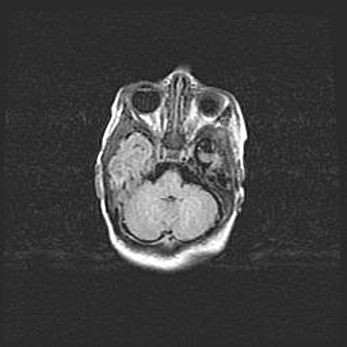

Множественные кисты обоих полушарий головного мозга, наибольшая из них в правой затылочной области. Ассиметричная атрофическая гидроцефалия.

Возраст: 7 месяцев

Вес: 5660 г

Пол: мужской

Окружность головы: 41,5 см

Срок гестации: 28-29 недель

Кисты головного мозга развиваются в результате многоочаговых некрозов вещества мозга и возникают вследствие перенесенной перинатальной инфекции, менингитов, энцефалитов, асфиксии, родовой травмы, расстройств мозгового кровообращения различного генеза. Образованию кист в веществе головного мозга плодов и новорожденных способствуют такие факторы, как высокое содержание в нем воды, недостаточная (или отсутствие) миелинизация и слабая астроглиальная реакция на повреждение.

Кисты могут сочетаться с гидроцефалией и другими поражениями головного мозга.